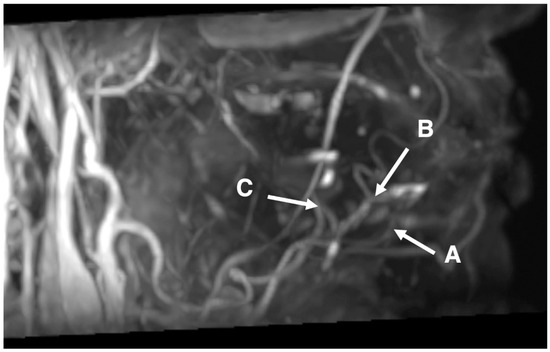

3.1. Conspicuity in the Visualization of the Branches of Lingual and Facial Arteries around the Lingual Sides of Mandibles Using SSFP with a Time–SLIP

3.3. Characteristics of Branches of Lingual and Facial Arteries Using SSFP with a Time–SLIP